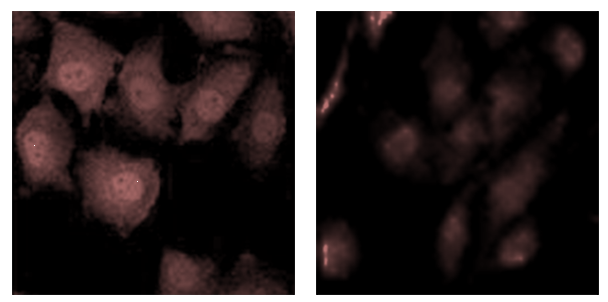

1.使用(共聚焦)荧光显微镜观察(定性检测) :

绿色荧光减弱,表明膜通道孔活性(MPTP) 增强

2.交付标准:荧光图片、比值、实验报告(实验步骤、试剂、仪器)